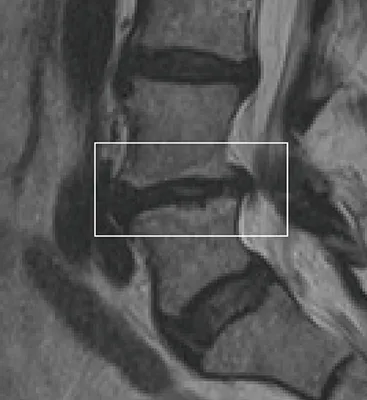

Vertebrogenic pain is a specific type of chronic low back pain that originates from damage to the vertebral endplates—the thin layers of tissue separating each spinal disc from the bones above and below. As these endplates deteriorate over time, often due to normal wear or disc degeneration, they can become inflamed and painful.

This condition is often accompanied by Modic changes—inflammatory changes visible on MRI that indicate endplate damage and are commonly associated with vertebrogenic pain.

✓Your MRI shows Modic changes, which indicate endplate inflammation